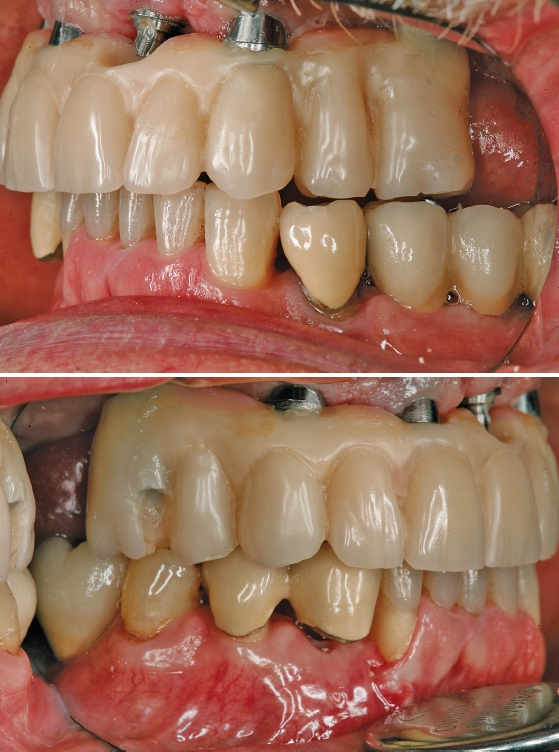

Eingliederung

Das Aufschrauben der definitiven Brücke gestaltete sich problemlos. Nach Abnahme der temporären Versorgung ist die fertiggestellte Brücke über die Prothetikkappen bzw. die Verbolzungen auf den Implantaten befestigt worden (Abb. 5 und 6). Bei den posterioren Implantaten wurde der Schraubenzugang vom Zahntechniker nach vestibulär – außerhalb des sichtbaren Bereichs – gelegt (Abb. 7 und 8). Die anderen Implantate wurden im palatinalen Bereich verschraubt (Abb. 9). Aufgrund der Drei-Punkt-Fixierung ist ein Verkippen oder das Rotieren des Zahnersatzes ausgeschlossen. Da die Schraube in der Sekundärkonstruktion „gefangen“ ist, wird die Anwendung im Mund erleichtert. Ein lästiges Einfädeln entfällt. Bereits mit zwei bis drei Umdrehungen ist eine Schraube fixiert. Weder ästhetisch noch funktionell treten Beeinträchtigungen auf.

Abschließend wurden die funktionellen, ästhetischen und parodontal- hygienischen Faktoren überprüft und dem Patienten entsprechende Hinweise zur adäquaten Reinigung des Zahnersatzes gegeben (Abb. 10 und 11). Bei einem regelmäßigen Recall (idealerweise aller drei Monate) kann die Brücke aufgrund der transversalen Verschraubung sehr einfach gelöst und alle erforderlichen Mundhygienemaßnahmen vorgenommen werden.